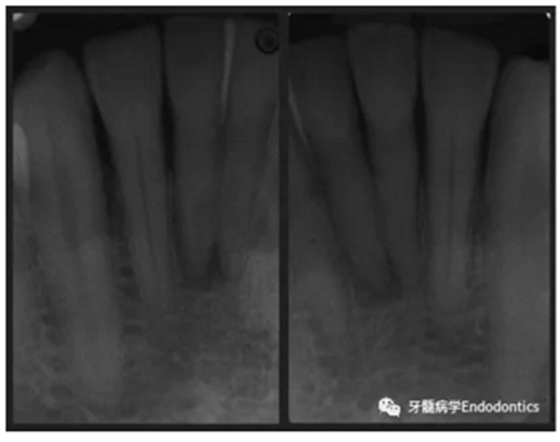

31、41叩痛明顯,牙冠變色(圖1)。溫度和牙髓電活力測(cè)試無反應(yīng)。兩張從不同角度拍攝的x線片顯示,相對(duì)于側(cè)切牙,雙側(cè)下中切牙都有嚴(yán)重的根管鈣化(圖2)。41有明顯根尖周暗影,31根尖周暗影不明顯。為進(jìn)一步證實(shí)31是否存在根尖周病變,同時(shí)精細(xì)觀察31、41的復(fù)雜結(jié)構(gòu),根據(jù)歐洲牙髓病學(xué)會(huì)CBCT應(yīng)用指南(2014),對(duì)患牙拍攝小視野、高分辨率CBCT。CBCT影像證實(shí)31、41均伴有根尖周炎和嚴(yán)重的根管鈣化(圖3)。距離根尖4mm可見根管影像。 由于患牙根管解剖結(jié)構(gòu)較為復(fù)雜,筆者決定使用特殊設(shè)計(jì)的微型鉆頭(直徑0.85mm)進(jìn)行“數(shù)字化導(dǎo)航牙髓治療”。 因此對(duì)下頜進(jìn)行口內(nèi)掃描(圖4)。用coDiagnostixTM軟件(Dental Wings Inc.,Montreal,Canada)將CBCT和口內(nèi)掃描的數(shù)據(jù)進(jìn)行處理,該軟件主要用于引導(dǎo)種植。通過該軟件對(duì)兩個(gè)掃描圖像進(jìn)行疊加后,虛擬鉆頭尖端沿牙長軸對(duì)準(zhǔn)根管下段可見部分(圖5)。三維檢查虛擬鉆的正確位置。

圖2. 31、41X線影像。

圖3.下頜前牙CBCT影像。